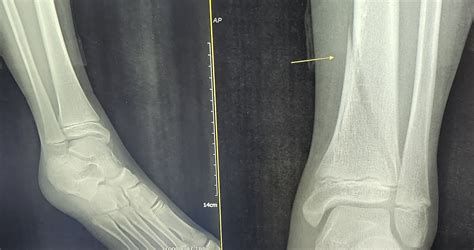

발 골절 수술 평균 비용은 얼마나 되나요

2025년 기준 발 골절 수술의 평균 비용은 약 1,650,000원입니다. 실제 사례를 보면 다음과 같은 범위를 보입니다:

- 최저 비용: 730,000원

- 최고 비용: 4,100,000원

- 평균 입원일수: 10.8일

이 수치는 발목을 제외한 발 골절(발등, 발가락 등)을 대상으로 전국 473개 의료기관(병원, 종합병원, 상급종합병원) 자료를 바탕으로 산출된 것으로, 건강보험이 적용된 기준입니다.

병원 규모, 골절 부위와 정도, 수술 방법, 비급여(특수 재료, 1인실 등) 유무, 입원 기간 등에 따라 비용은 큰 차이가 있을 수 있으므로, 실제 진료 전에는 해당 병원에 문의하여 정확한 견적을 확인하는 것이 안전합니다.

특히 발가락 등 비교적 단순한 골절 및 핀 제거, 짧은 입원만 필요한 경우에는 이보다 저렴하게(수십~수백만 원선) 나올 수도 있습니다